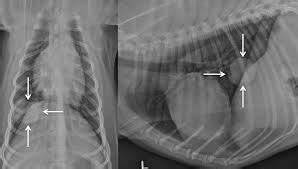

Lung Cancer in Dogs (Symptoms and Treatment) - CancerOz from 4.bp.blogspot.com The average survival is closer to 8 months for dogs with big tumors, and 2 months if there is metastasis. For many dogs, the recommended treatment is surgery. Because spread to the lung occurs late in the clinical course of a malignant tumor, the outlook is poor. Computed tomography (ct scan) can be performed to identify some of these lung tumors. Your dog might also receive chemotherapy and radiation. In order to accurately and definitively the diagnosis of primary lung cancer in your dog, your veterinarian will perform a physical examination, as well as the order of several tests. If your dog has fewer than four lung nodules, it's possible for your vet to surgically remove them to increase your dog's life span, according to the animal surgical center of michigan. While both primary lung cancer and metastatic lung cancer have similar symptoms, coughing tends to be less common with metastatic tumors.

Metastatic NSCLC: When It's Time to Change Treatment from img.webmd.com Especially consider artemisinin for lymphoma, osteosarcoma, and other cancers that fall under the heading of phlegm nodule cancers. First of all, surgical removal is the most straightforward way of eliminating the cancerous cells because it is a way of literally removing the cancerous lung tumor. However, a complete resection of the affected lung lobe is often the only way to stop the spread of this highly metastatic cancer. It is also much more common than primary lung tumors in pets, so it is important to be as certain as possible about the. Radiation therapy is sometimes used for the treatment of lung cancer in dogs depending upon the proximity of the lung tumor to the heart. While both primary lung cancer and metastatic lung cancer have similar symptoms, coughing tends to be less common with metastatic tumors. Lung cancer in dogs and cats compared to people, primary lung cancer is very uncommon in dogs. Computed tomography (ct scan) can be performed to identify some of these lung tumors.

They can be detected on chest radiographs or computed tomography (ct) scanning.